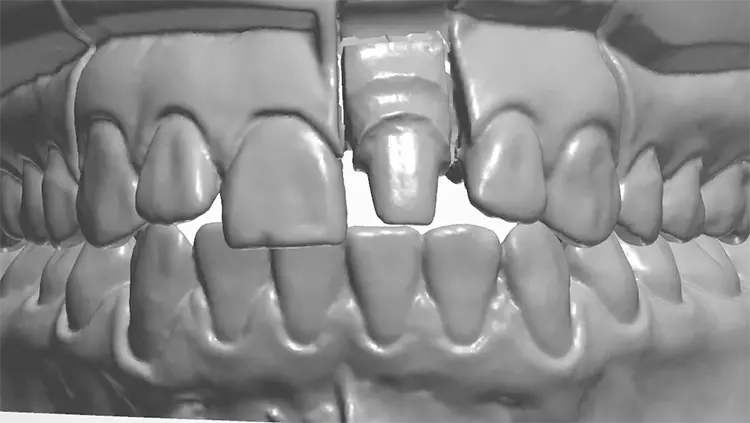

Auf den vorab hergestellten Situationsmodellen wurde für die provisorische Versorgung eine Tiefziehfolie für den Oberkiefer hergestellt. Es erfolgte die schonende Abnahme der Einzelzahnrestauration und die Entfernung des Befestigungsmaterials.

Die vorgefundene Präparation konnte im labialen Bereich in 3 Ebenen anatomisch reduziert und optimiert werden. Bei der Platzierung des zirkulären Präparationsrandes war die „biologische Breite“ nicht berücksichtigt worden und der Kronenrand lag deutlich subgingival.

Die Gingiva wurde mithilfe eines Retraktionsfadens vorsichtig verdrängt und die zirkuläre Präparation mit einer ausgeprägten Hohlkehle klar definiert. Beim Langzeitprovisorium, welches man in der Praxis herstellte, wurden sämtliche ästhetischen und funktionellen Parameter berücksichtigt und die „äußere Hülle“ der definitiven Krone festgelegt.

Gleichzeitig wurde mit den initial angefertigten Silikonschlüsseln die anatomische Reduktion des Zahnes 21 visualisiert und die labiale Reduktion in 3 Ebenen bewertet. Die Zielfarbe der Restauration und die Stumpffarbe wurden vor der Abformung für das zahntechnische Labor bestimmt und mit Fotos dokumentiert. Nach Darstellung des Präparationsrandes mittels Retraktionsfaden und Teflonband erfolgte eine klassische Abformung mithilfe eines individuellen Löffels und eines Polyethermaterials (Abb. 11–20).